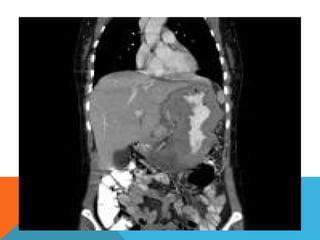

Computed tomography

Typically gastric lymphomas demonstrate marked

thickening of the stomach wall (2-4cm) with extensive

lateral extension of the tumour (i.e. along the wall of

the stomach) representing submucosal spread.

 Submucosal spread may

 Encompasses the majority of the stomach giving a

linitis plastica appearance.

 Can extend across the pylorus into the duodenum

and superiorly into the oesophagus.

 uncommon for lymphoma to result in

gastric outlet obstruction

Computed tomography Typically gastriclymphomas demonstrate marked thickening of the stomach wall (2-4cm) with extensive lateral extension of the tumour (i.e. along the wall of the stomach) representing submucosal spread.

 Submucosal spreadmay  Encompasses the majority of the stomach giving a linitis plastica appearance.  Can extend across the pylorus into the duodenum and superiorly into the oesophagus.  uncommon for lymphoma to result in gastric outlet obstruction